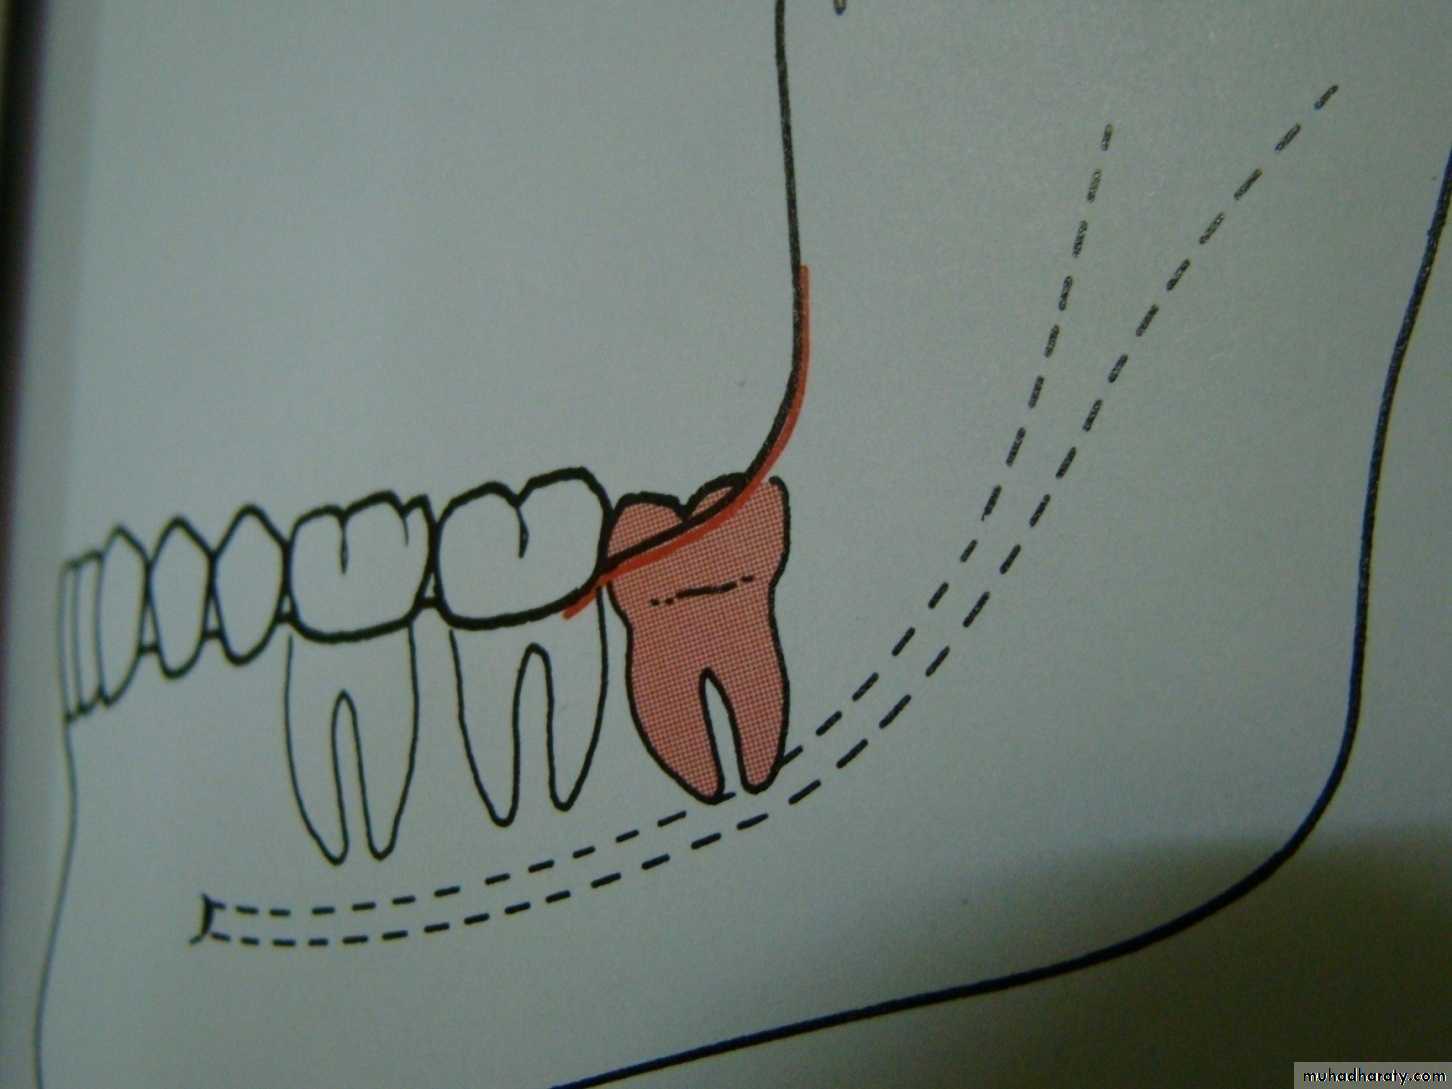

mesioangular

1-White line: it is an imaginary line draw along the occlusal surface of erupted first and second molars extend posteriorly over 3rd molar region . Its benefit is to determine the angulations of an impacted tooth and its relationship with occlusal surface of erupted 2nd molar(depth).2- Amber line: It is a line drawn from the surface of bone laying distally to the 8 and to the crest of interdental septum or alveolar septum between 6 and 7. it determine the amount of bone removal

3-Red line : it is draw perpendicular from amber line to an imaginary point of elevator application located mesially to the CEJ except in Disto angular impaction it is distally located . It is used to measure the depth of the impacted tooth.

Note: Any tooth with red line length more than (5 mm) it is better to remove it under G.A.